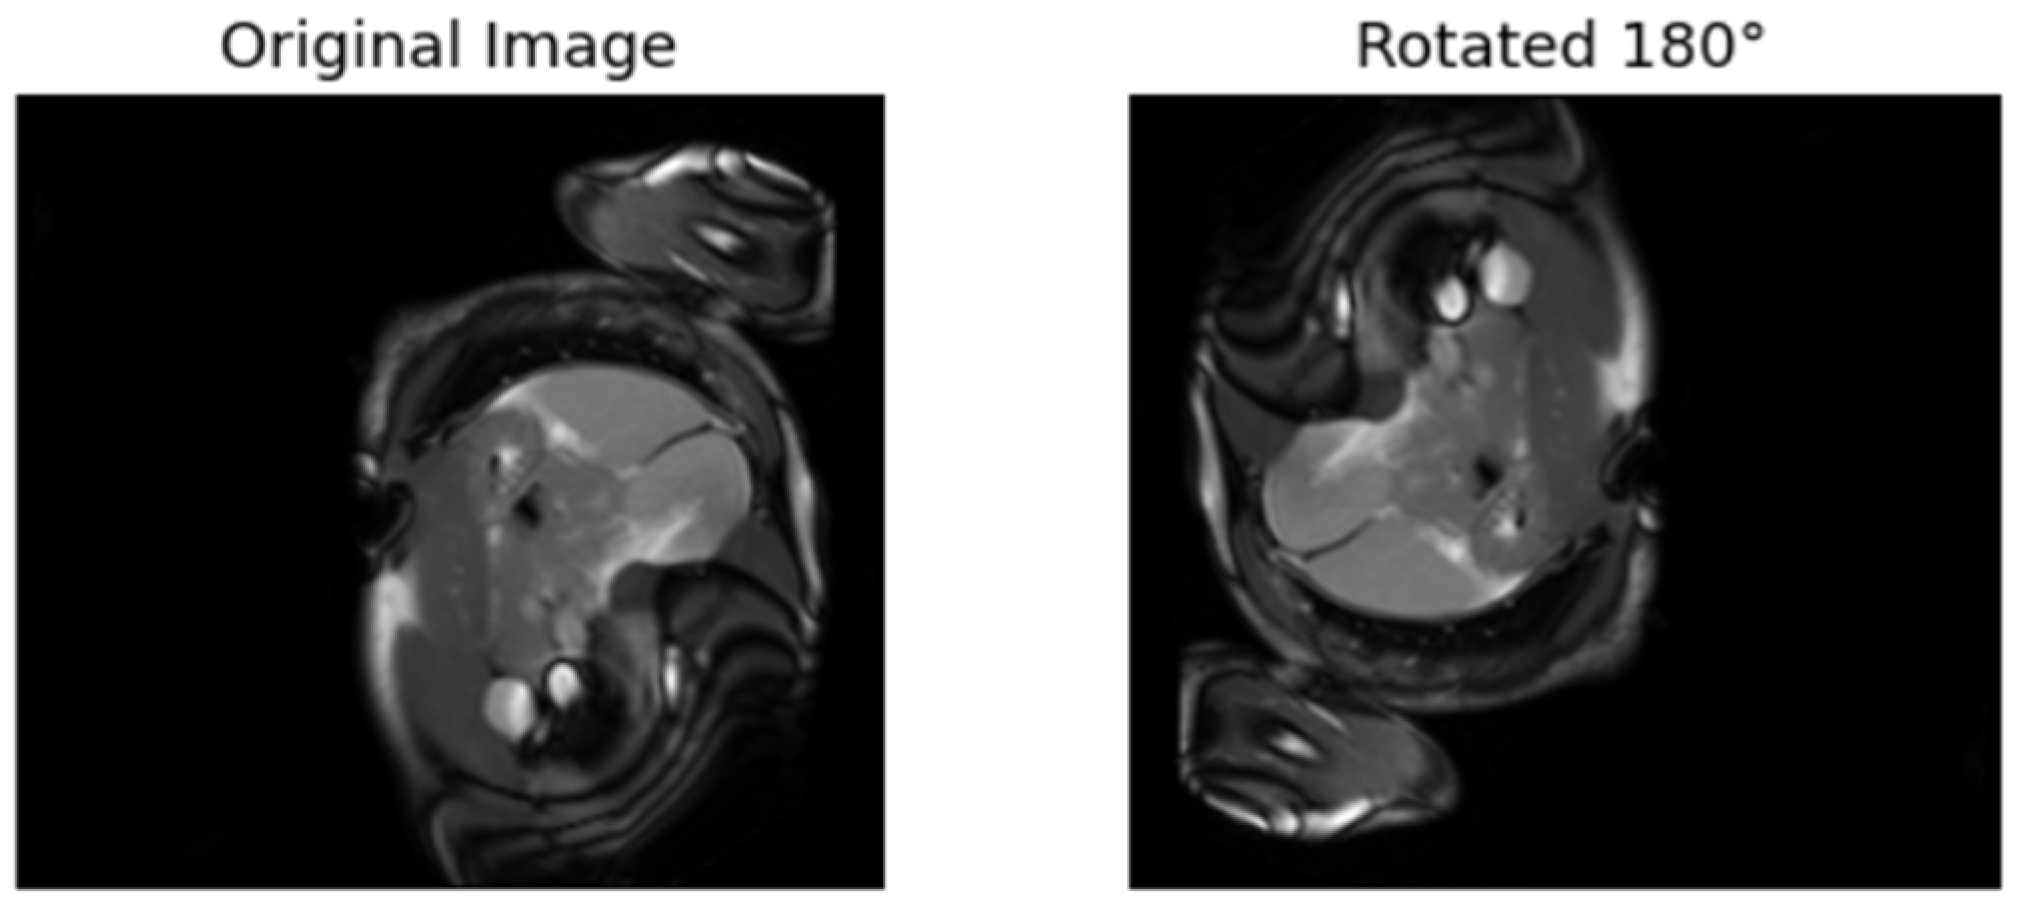

| [17] | Rotates the images 90°, 180°, etc. The model is trained to predict the rotation. | Labels are from the rotated angles |